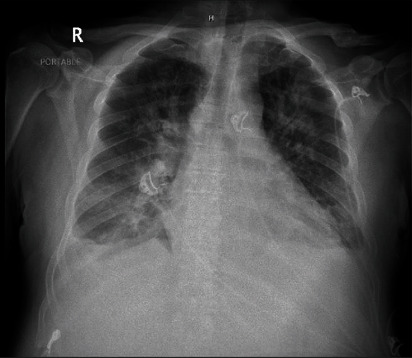

Abstract Image